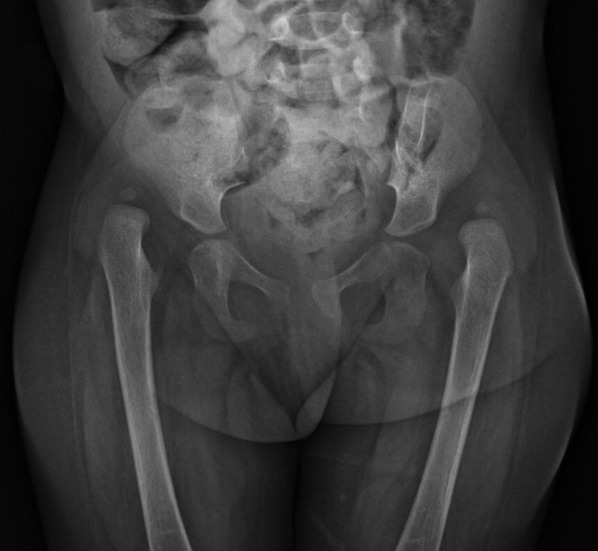

Clinical case: Female patient, one year and three months old, presents hyperextension of the knees. On physical examination, the patient presents bilateral cleft palate, absence of soft palate, cleft lip and tracheostomy, positive Hart sign, negative Peter Bade sign and fixed retrocurved knees with limited range of motion. Radiographs reveal bilateral hip dislocation and knee dislocation. Karyotype analysis confirms the diagnosis of CdCS.